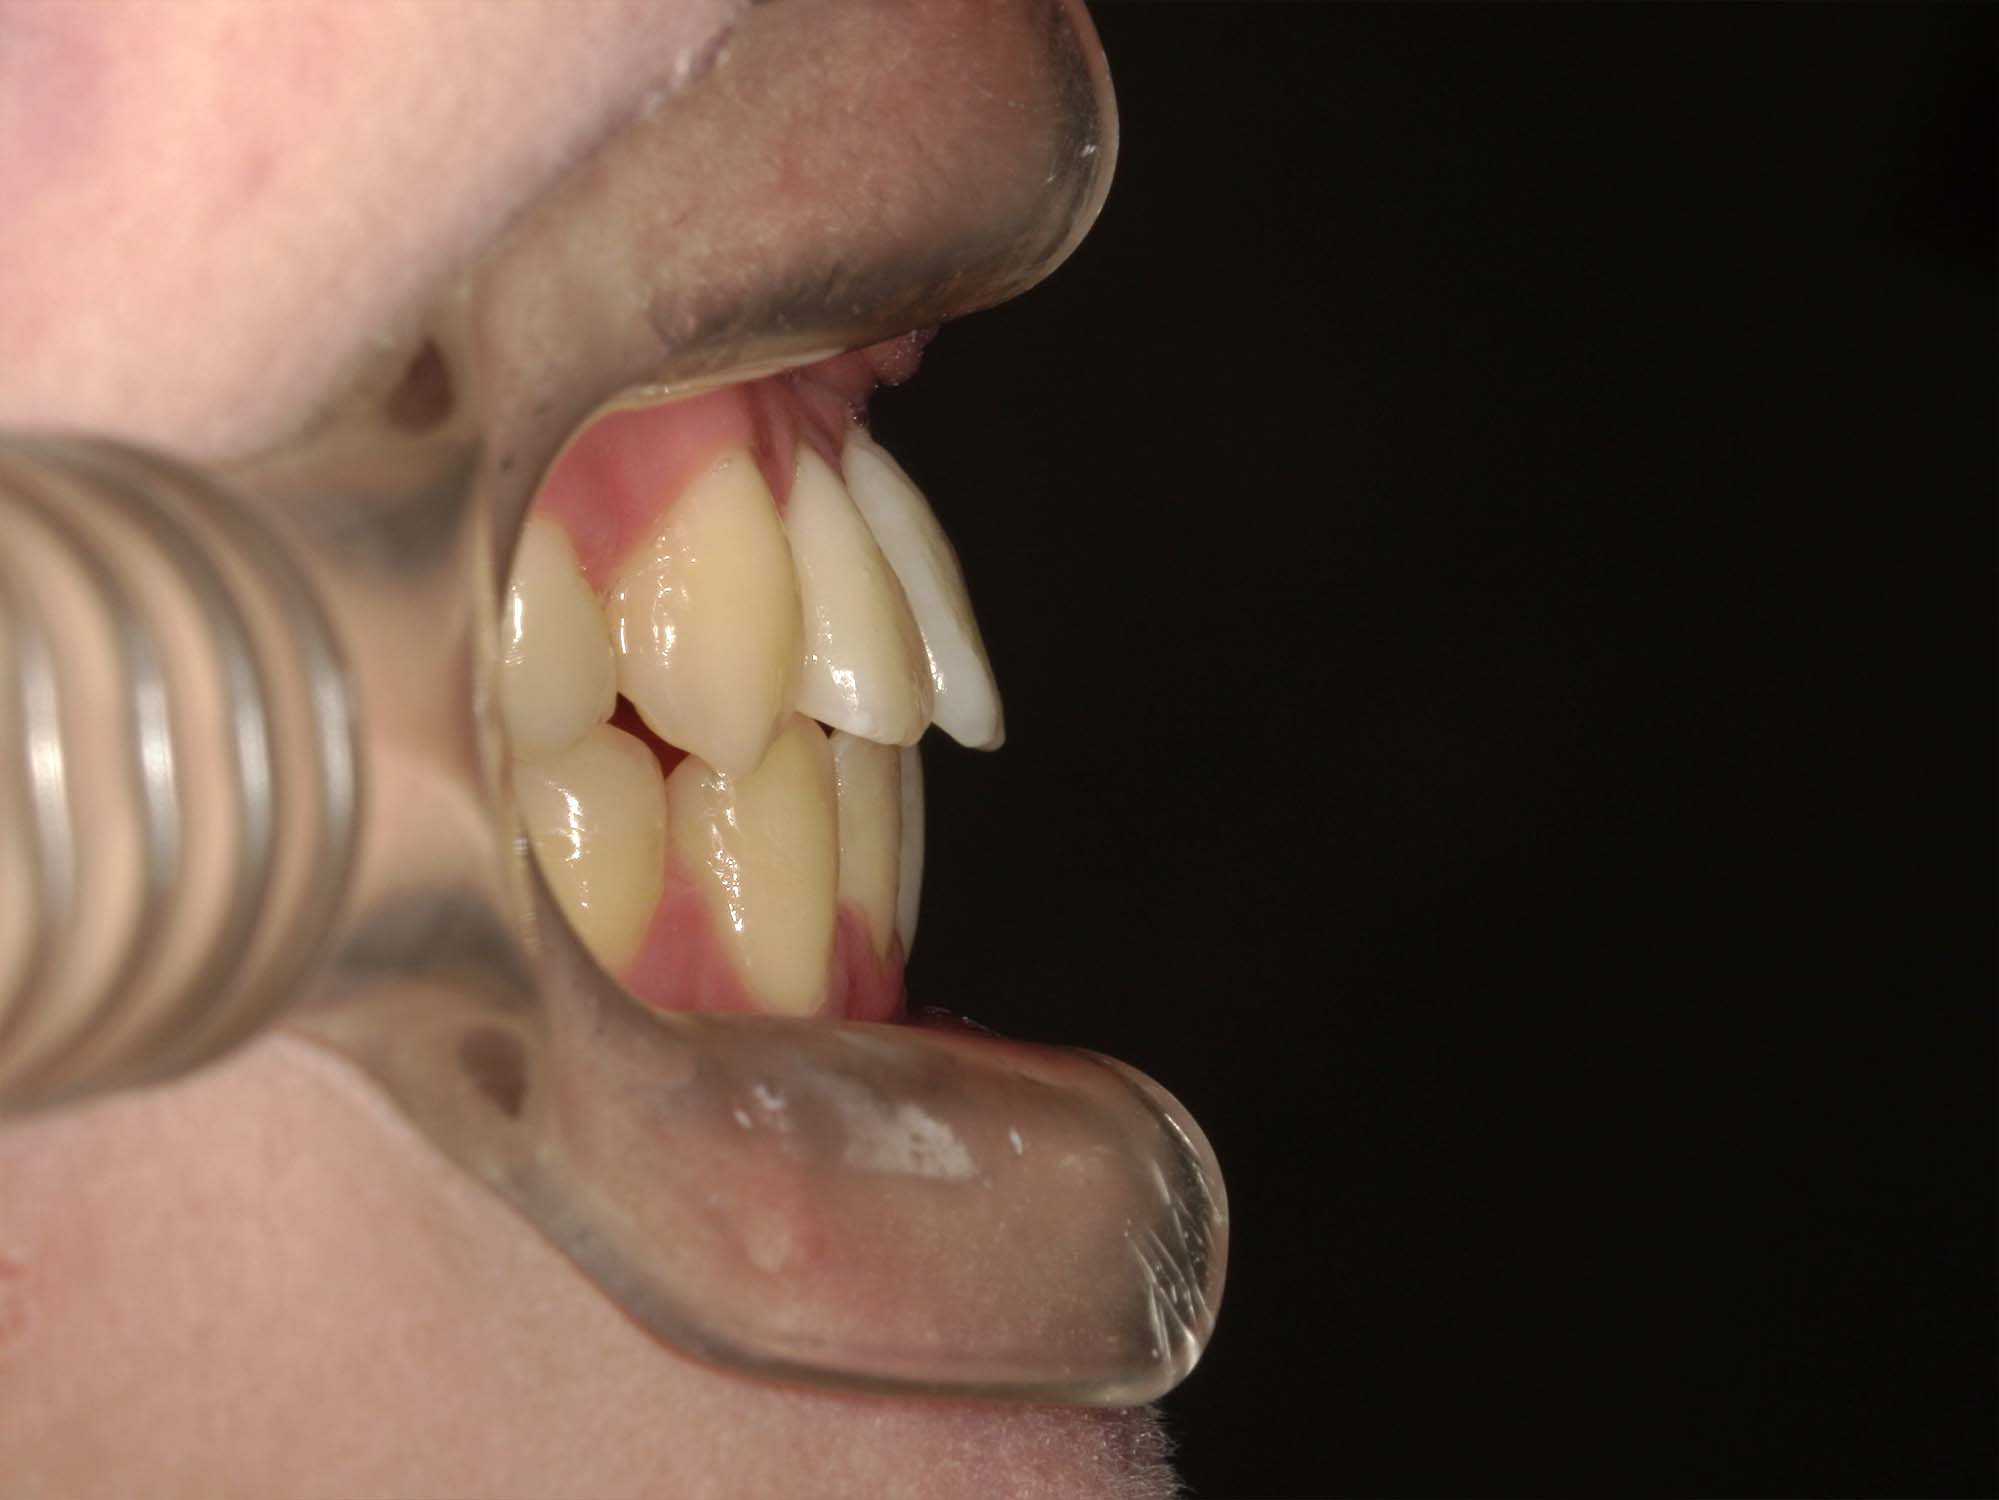

| 年齢・性別 | 25歳女性 |

|---|---|

| 主訴 | 前歯の歯並びの乱れ(叢生)を気にされて来院された25歳女性。咬み合わせや審美的な改善を希望されていました。 |

| 治療期間・回数 | 4年5ヶ月・30回 |

| 費用 | 1100,000円(税別) |